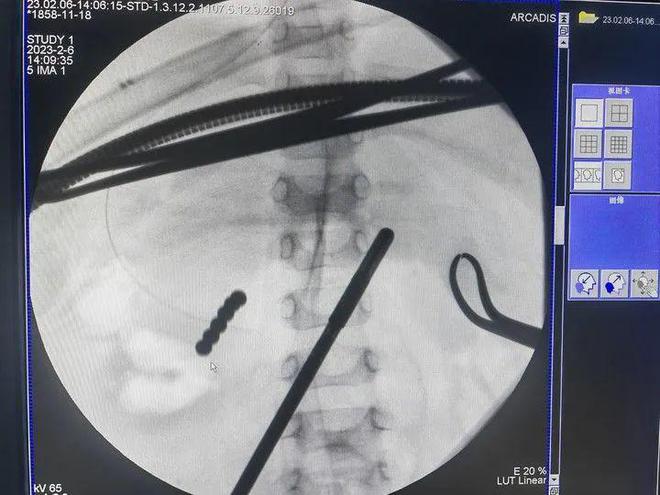

拍片显示

幼童腹部有一串金属物

原来,研研在玩磁力球的时候害怕被哥哥抢走,就放入口中吞食了下去。“不到十分钟,孩子就吵着难受,恶心呕吐没精神。”研研的妈妈赶紧把他送到医院,拍片显示研研腹部有一串金属物。

研研的腹部显示有一串金属物

腹腔镜加C型臂辅助

6颗磁力球成功手术取出

然而,保守治疗几天后,诊断显示异物位置固定不变,很有可能无法自动排出。2月6日,研研接受了异物取出手术。 曲修水主任医师在腹腔镜加C型臂的辅助下,通过一个3厘米的切口,将6颗磁力球成功取出。

医生为研研进行异物取出手术